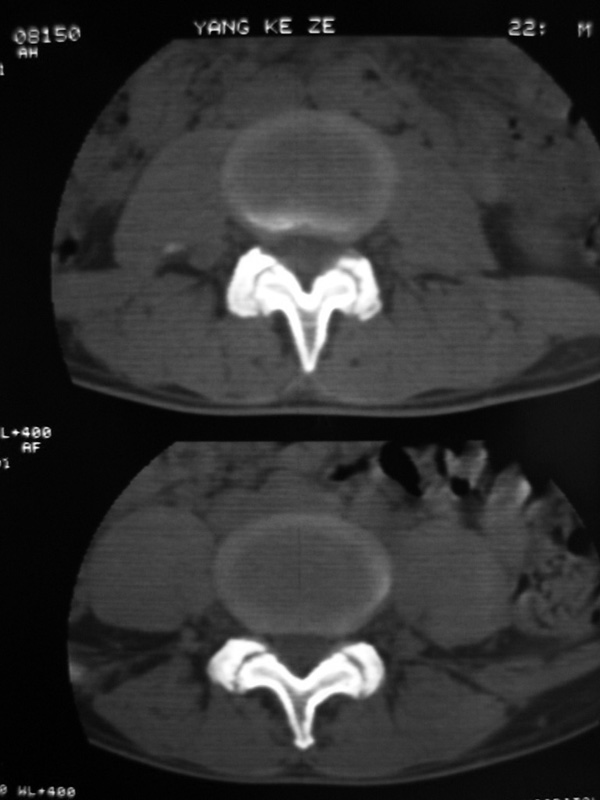

以下是引用w_jianhua在2007-3-8 11:14:00的发言:[br]椎小关节及右侧骶髂关节关节面毛糙,间隙不规则狭窄,骨皮质增生硬化,支持强直性脊柱炎,并椎间盘膨出

以下是引用fumaogui在2007-3-8 8:40:00的发言:[br]腰椎椎间关节增生硬化,关节间隙变窄,右侧骶髂关节间隙变窄,关节面硬化[br]考虑强直性脊柱炎.建议结合化验查:c--反应蛋白和类风湿因子.